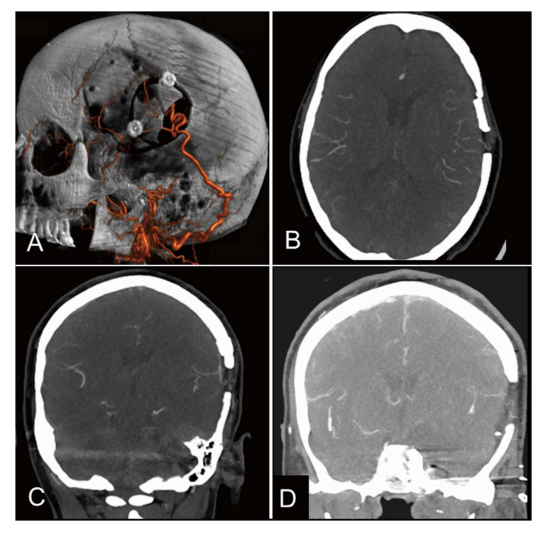

搭桥术后1周行DSA复查,确认吻合口及移植血管通畅(图5)

图5.OA-MCA搭桥术后影像。D:肿瘤切除术后(搭桥术后1.5个月)即刻CTA示OA-MCA搭桥仍通畅。

搭桥术后患者神经功能障碍部分改善。于搭桥术后1.5个月(即血管内ICA闭塞后2.5个月)实施肿瘤全切除(图6)。